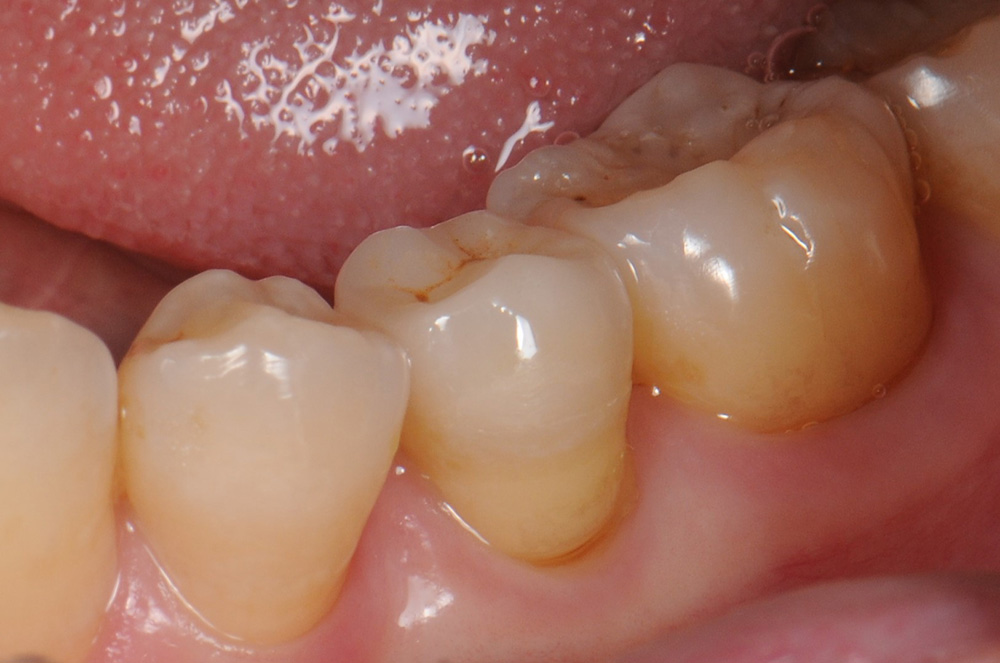

case9 症例(セラミックブリッジ)

治療前

治療後

| 費用(税込み) | 198,000円 |

|---|---|

| メリット・デメリット | 歯を削る、一時的に知覚過敏になる |

| 治療回数 | 5-6回(歯肉・仮歯の調整含む) |

| 主訴 | 奥歯が無い |